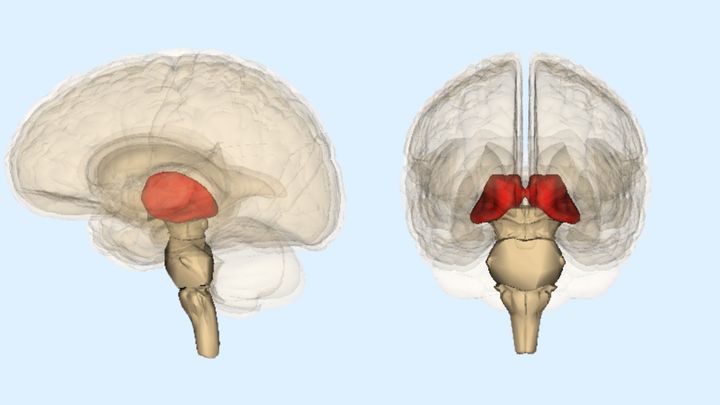

脳の詳しい検査を行ったところ、脳卒中によって脳の奥深くにある「視床」という部位が損傷を受けていることが明らかになったのです。

視床とは脳の中で特に重要な役割を持つ、小さな「ハブ(中継地点)」のような場所です。

この視床は感情や注意力、記憶、さらに感覚情報や思考を統合するなど、脳全体の機能を円滑に保つための司令塔のような役割を担っています。

特に、左右に一つずつある視床のうち、右側の視床は感情や社会的な判断をコントロールする脳のネットワークと深くつながっているとされています。

今回の検査で、女性の脳卒中は非常に珍しいタイプで、左右両方の視床に損傷を与えていることが判明しましたが、そのうち特に右側の視床の損傷が強く見られました。

医師たちはこの右側の視床へのダメージが、嫉妬妄想という特殊な精神症状に直接的に関係している可能性が高いと判断し「脳卒中によるオセロ症候群(病的嫉妬妄想)」と正式に診断されました。